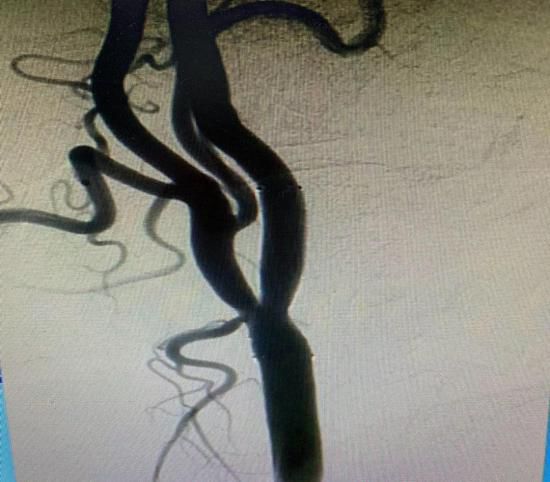

(1)2018年12月12日开展第一例肾动脉支架植入术。

患者:赵某 男性 49岁 岳村镇

图片

术前

术后